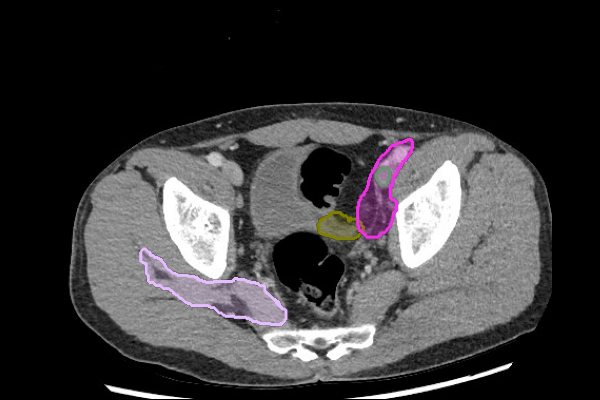

Stones

- Even without hydronephrosis, consider the possibility of ureteral calculi and attempt to follow the course of the ureters to screen for stones.

- Look carefully for small stones in the ureter/UVJ. Familiarize yourself with the normal location of the ureterovesical junctions and the configuration of the distal ureter to discriminate phleboliths from potential distal ureteral calculi